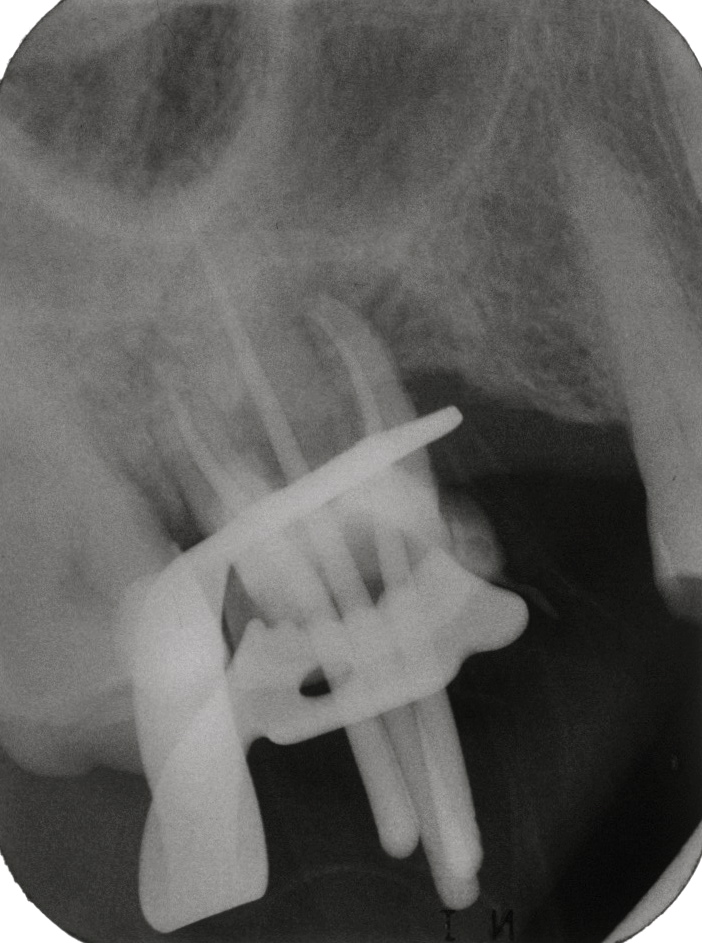

So, die Feile war nun dargestellt. Zumindest der obere Ende war im mesio-buccalen Kanal zu erkennen.

Eine gespitzte NSK E5 Ultraschall-Spitze wurde aufgeschraubt und los ging es mit dem zirkulären Freilegen der Feile. Ich mache es ohne Wasser, die Helferin pustet den entstehenden Staub mit dem Luftbläser weg, so dass ich gut sehen kann, was ich gerade mache.

Schon nach kurzer Zeit war die Feile nicht mehr zu sehen. Also Spülung und wieder trockenen.

Die Feile war immer noch nicht zu sehen.

Mögliche Ursachen:

• die Feile hat sich schon gelöst und ist herausgeflogen – bei der Lage und Länge der Feile eher unwahrscheinlich, ausserdem sieht man das normalerweise

• die Feile liegt anders als vermutet

Wenn die Feile anders liegt als vermutet, muss man wieder suchen.

Aber wo?

Erste Frage:

Wo liegt sie sicher nicht?

Das ist relativ leicht zu beantworten.

Sie wird nicht buccal liegen, da im unteren 7er, wenn er zwei Wurzeln hat – und Hinweise auf drei oder mehr Wurzeln gab es auf dem Röntgenbild nicht, der mb Kanal eine starke Krümmung nach zentral aufweist.

Die mesiale und distale Richtung kann man mit dem Röntgenbild ausschliessen.

Also muss ich nach zentral weitersuchen. Der Kanaleingang wurde mit dem Rosenbohrer nach zentral erweitert – und schon war die Feile wieder zu sehen.

Nun musste die Feile weiter freigelegt werden. Es wird wieder zirkulär Dentin abgetragen. Sobald buccal vom Fragment Dentin abgetragen wurde, und ein Freiraum entstand, drückte sich das Fragment wieder nach buccal an die Wand. Das heisst ganz klar, dass das Fragment gebogen ist, und es sich gerade richtet, sobald es die Möglichkeit dazu hat.

Das heisst aber auch, dass, wenn buccal weiter Dentin abgetragen wird bis das Fragment spannungsfrei ist, buccal mit Sicherheit die Wurzel perforiert wird.

Also muss das Dentin dort abgetragen werden, wo die Perforationsgefahr am geringsten ist. Und das ist an der Innenkurvatur des Fragmentes.

So wurde das Fragment freigelegt, indem nach zentral Dentin abpräpariert wurde. Nach einiger Zeit hat sich das Fragment im Kanal entspannt und es lag locker, es kam jedoch nicht um die Kurve, erst nach weiterem Substanzabtrag konnte sich die abgebrochene Feilenspitze ganz lösen.

Im Laufe der Freilegung wurde klar, wie stark die Krümmung des Kanals nach zentral wirklich war.

Anschliessend wurde mit NaOCl desinfiziert und als Medikament Calciumhydroxid eingelegt. Zum nächsten Termin wird nochmals desinfiziert und abgefüllt.